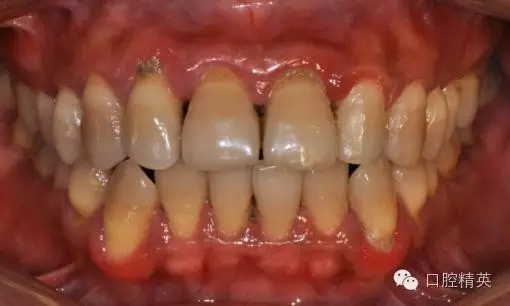

本病例 :女 34歲,主訴刷牙出血,覺牙齒輕度松動一年。

檢查見大量齦上及齦下結(jié)石,探診出血,牙周袋較深,32-42 II度松動。X線片顯示牙槽骨水平吸收。

診斷:成人慢性廣泛性中度牙周炎。

治療前: